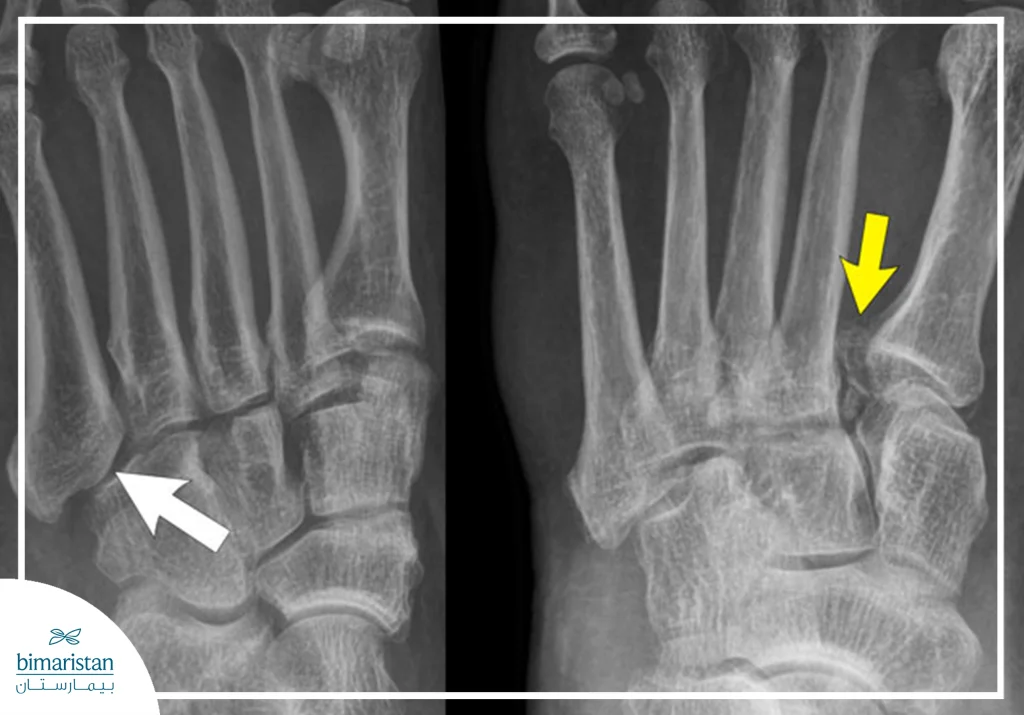

التصوير بالأشعة السينية

تُعد الأشعة السينية الوسيلة الأساسية لتشخيص معظم حالات كسور القدم، إذ تُظهر موضع الكسر بدقة وتُساعد في تحديد ما إذا كان الكسر مغلقاً أو مفتوحاً، بسيطاً أو متعدداً. تُستخدم عادة كخيار أول بعد الفحص السريري، وهي ضرورية لتوجيه قرار الطبيب حول التثبيت أو الجراحة، في كثير من الحالات يُجرى التصوير من أكثر من زاوية للحصول على رؤية شاملة لتركيب العظام.